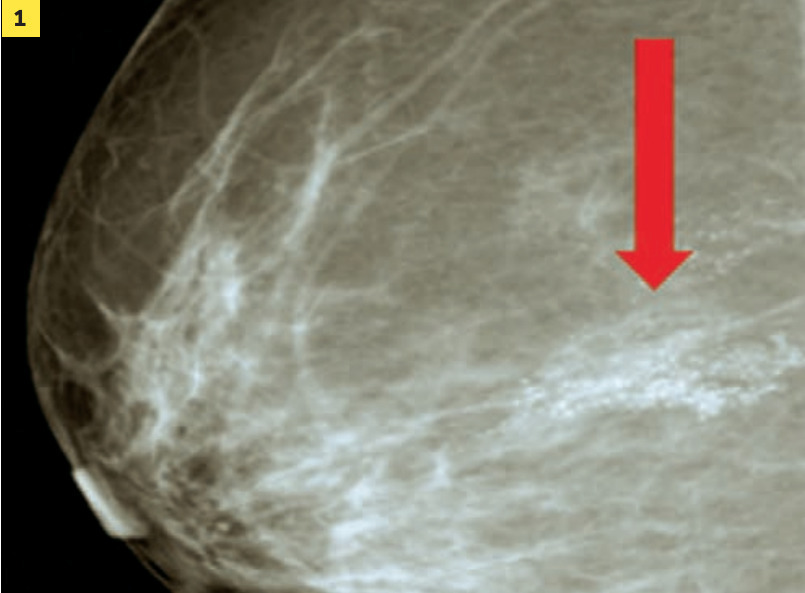

Mammographie et échographie des seins et des creux axillaires sont fondamentales pour le diagnostic et la caractérisation morphologique. Les anomalies retrouvées sont uniquement mammographiques dans le cas particulier de foyer de microcalcifications (isolé ou étendu dans le sein ; fig. 1) ou seulement échographiques en cas de nodule tissulaire ; dans la majorité des cas, le cancer est vu à l’écho et à la mammographie. Les régions axillaires sont systématiquement analysées avec les 2 techniques.

En cas de diagnostic positif, on recherche à l’interrogatoire des symptômes d’apparition récente : fatigue, amaigrissement, douleur osseuse élective, insomniante, non calmée par des antalgiques simples (fig. 2 ; métastase osseuse avec risque neurologique par lyse complète de C3). Plus rarement, la patiente se plaint d’un essoufflement, un ptosis (syndrome paranéoplasique), une distension abdominale (ascite et localisation péritonéale).